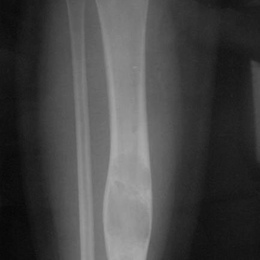

Radiographic imaging is used to help form a diagnosis of ABC. These include X-Ray, MRI, CT and Bone Scans

An example of an Adamantinoma X-Ray is shown.

98A) Plain AP X Ray Of Right Tibia Adamantinoma